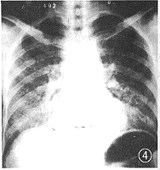

图4 肾移植后合并急性粟粒型肺结核

2.急性粟粒型肺结核:4例,为两肺弥漫分布的多发粟粒病变(图4)。